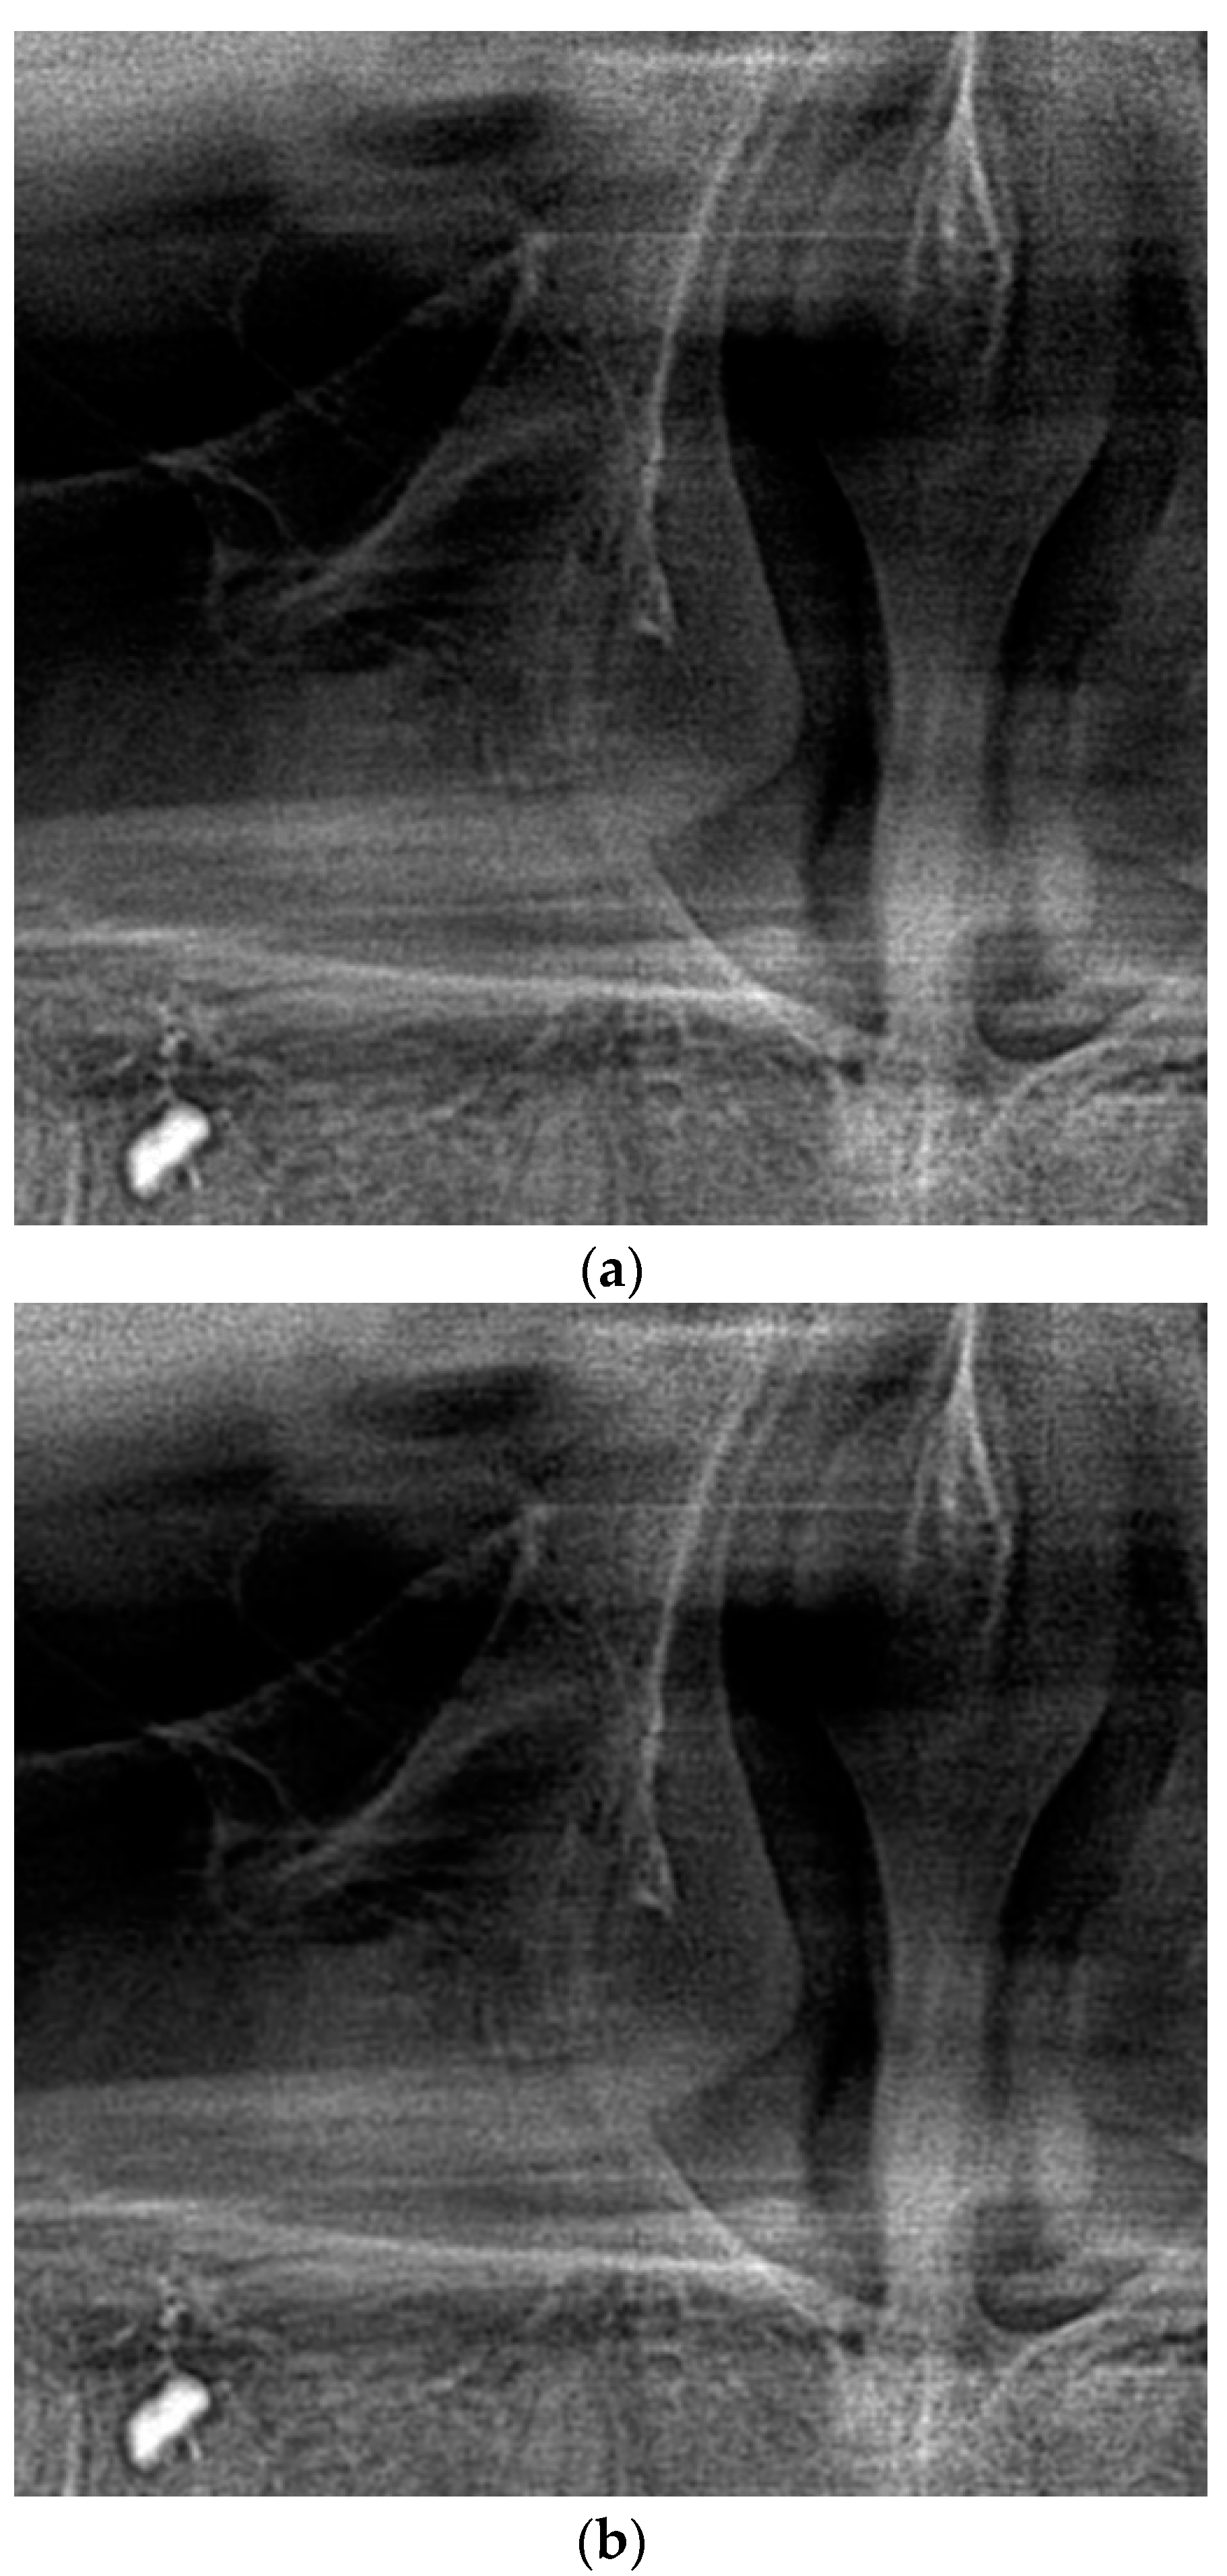

Visually, in most cases, no differences were detected (see an example in Figure 7). Even in the cases when minor changes were detected (less than 3% of all cases), they were not related to degradation of any useful diagnostic information or artifacts (some noise suppression has been noticed). Thus, the obtained results showed no differences that should influence diagnose statement, and compressed images were qualified the same as the original according to the Clinical Image Quality Evaluation Chart and dental specialists’ evaluation.

Figure 7.

A fragment of dental image before (a) and after (b) compression with the recommended QS, CR = 13.5.